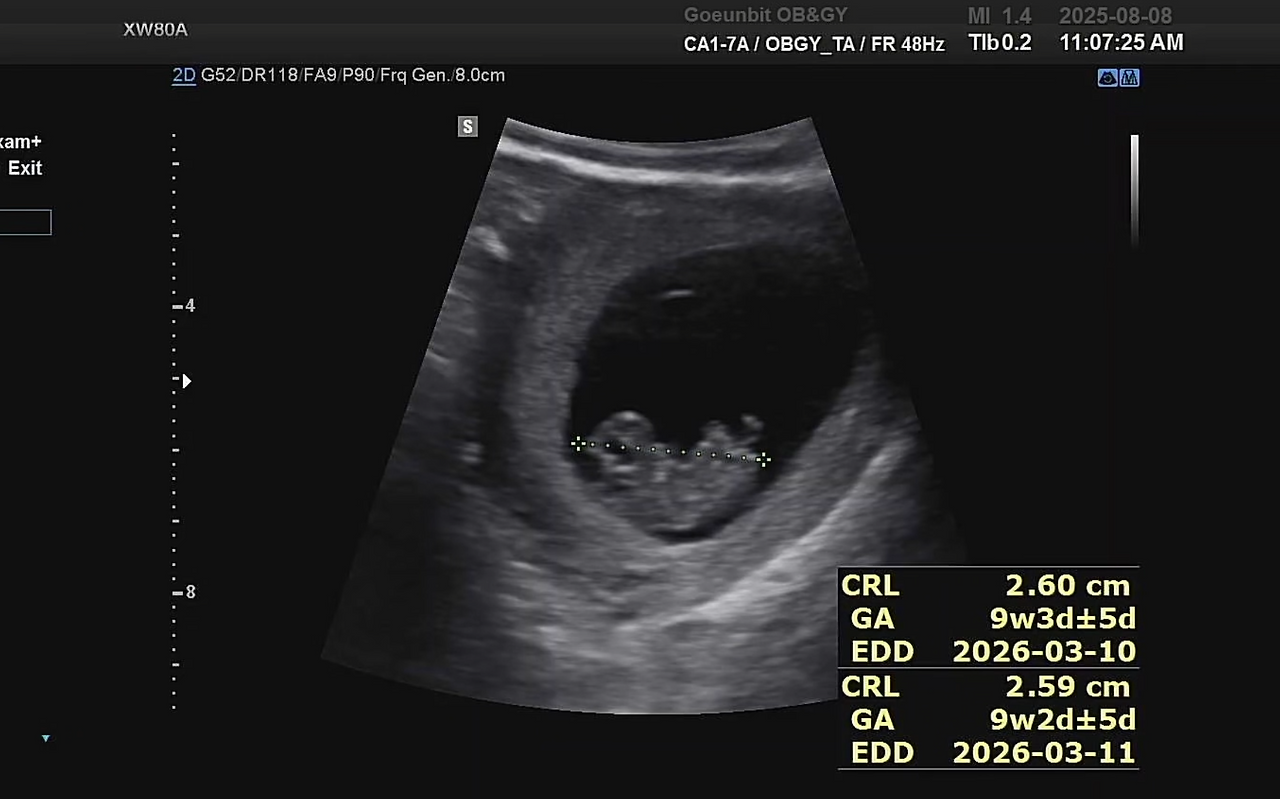

2주 만에 병원에 가서 배로 초음파를 봤지만, 느낀 건 “아직 잘 있구나” 하는 안도감뿐이었다.

내 눈에는 여전히 희미한 그림자일 뿐, 다른 산모들이 보여주는 귀여운 젤리곰은 보이지 않았다.

10주 차